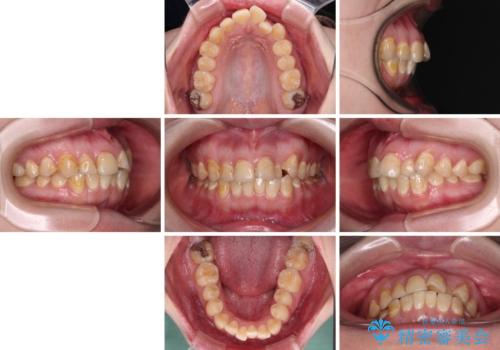

- 前歯のデコボコとクロスバイトが気になり、インビザラインによる矯正治療を希望して来院された患者様です。

上顎側切歯(上の真ん中から2番目の歯)が舌側転位している場合、無理して動かそうとすると歯髄壊死を起こすリスクが高い印象があります。

インビザライン単体でも治療は可能ですが、安全策としてインビザラインで歯列を移動する前に上顎前歯をワイヤー矯正で整え、その後上下歯列をインビザラインにて矯正治療を行うこととしました。

舌側転位している側切歯特有の、切縁の位置が不揃いであったり、根元が内側に引っ込んだ状態であったりという、インビザライン独特の仕上がりになることなく、きれいに整った歯列とすることができました。